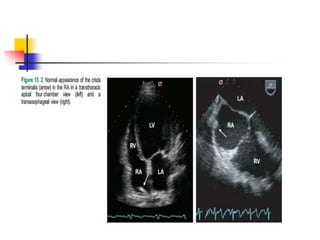

Crista Terminalis

 Crista terminalis is a well-defined fibromuscular ridge

separating a smooth sinus venarum and trabeculated

RA.

 Externally, it corresponds to the sulcus terminalis,

and internally, it extends from SVC to IVC along the

lateral RA wall.

 Embryologically, crista terminalis develops from the

septum spurium, which corresponds to the fused

boundary between embryonic sinus venosus and RA

proper.

 Prominent crista terminalis may be confused for RA

tumor on TTE.

 Echo findings s/o prominent crista terminalis instead

of tumor are as following:

 a nodular mass of similar echogenicity with adjacent

myocardium;

 the location on posterolateral wall of RA near the

SVC, which corresponds to the course of crista

terminalis connecting the SVC and IVC;

 the phasic change in size becoming thicker or larger

during atrial systole.

 Bicaval view of TEE best visualizes the crista

terminalis.